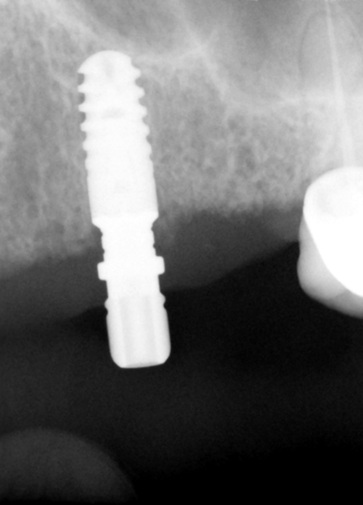

ANKYLOS® C implants of dimension B9.5(4.5 x 9.5) in region of 23 and A11.5 (3.5 x 11.5) in region of 13 were placed using the standard protocol [Table/Fig-3,4].

Radiograph showing implant in 13 region

Radiograph showing implant in 23 region

After three months of healing period, radiographs demonstrated successful oseointegration of the implants placed.